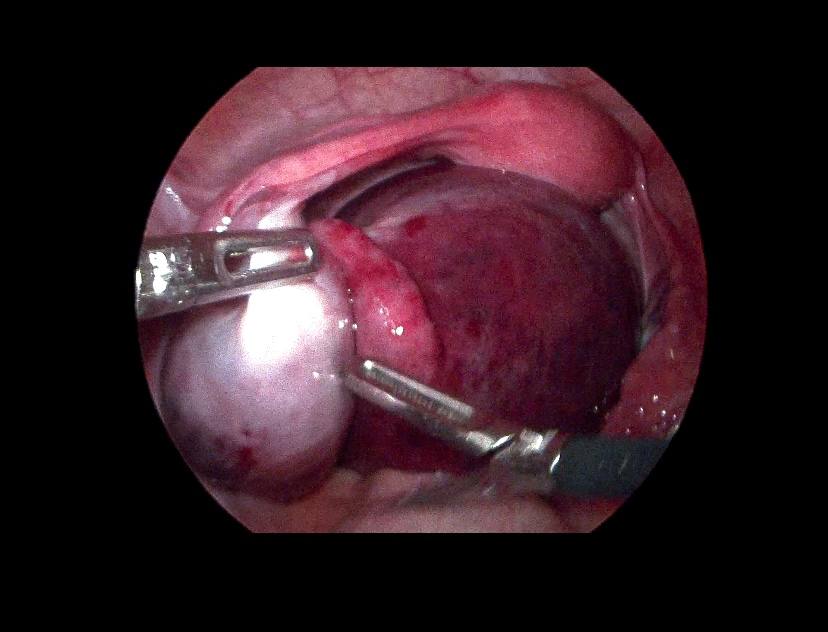

Left ovarian avascular cystic mass 71x68mm , with adjacent left adnexal mass 30x30mm , picture mostly of twisted ovarian pedicle , associated with free fluid >40ml , please for further study to excluded other pathology

Lt ovary is enlarged and edematous, contains 7cm thin wall unilocular cyst “ORADS 1”, there is twisting of its vascular pedicle, picture of ovarian torsion.

operation